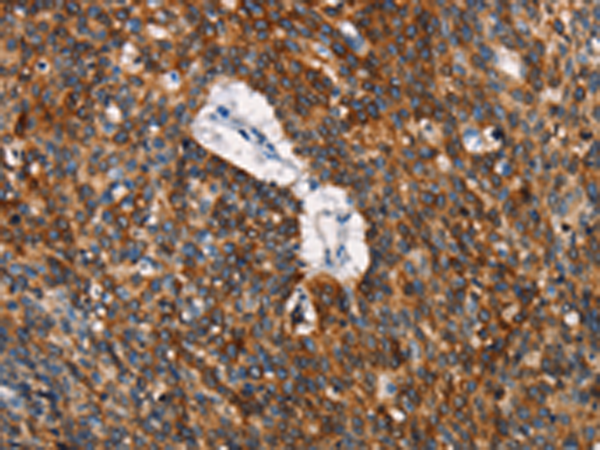

分类: 科研抗体货号: P11261别名: HGFR; AUTS9; RCCP2; c-Met应用: IHC反应种属: Human, Mouse, Rat